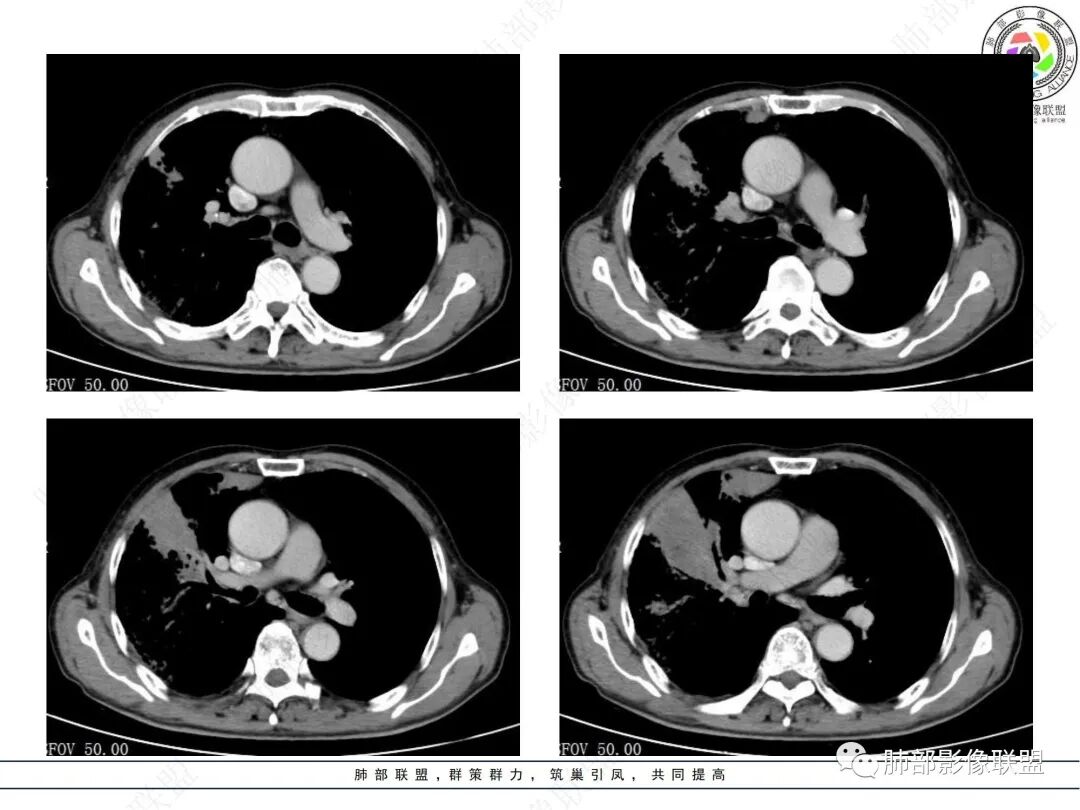

右肺上叶实变,宽基底与胸膜相连,邻近胸膜积液,上叶支气管阻塞,不均匀强化,血管显示可,局部坏死环形强化,可见气泡,考虑慢性炎症伴脓肿,放线菌?鉴别腺癌

右肺上叶尖段大片状实变,近肺门侧支气管闭塞,并可见病灶内部有片状液化坏死区,有空泡气体,病灶紧贴胸膜,胸膜反应性增厚,伴有少见积液,增强扫描内部不均匀强化,血管走形正常。影像符合慢性化脓性感染。

右肺上叶大片实变影,内密度不均匀,可见坏死环形强化,支气管被粘液栓阻塞,首先考虑感染性病变,奴卡?放线菌感染?

右肺上叶大片实变,密度不均,近端环形强化并见空泡,病灶与胸膜广基相连,之间并可见积液,考虑放线菌,鉴别腺癌

晨读:右肺上叶实变,密度欠均匀,不均匀强化,内血管走形可,近端环形强化并见空泡,考虑放线菌可能,鉴别腺癌

右主支气管周围多发淋巴结肿大融合(提示右主支气管有外受压变窄),右肺上叶尖前不张,内见支气管粘液栓和坏死及环形强化特点,邻近胸膜增厚及右肺上叶后段支气管扭曲及狭窄后扩张,周边索条纤维化,综合TB表现,超声支气管镜检查。

老年女性患者胸痛咳嗽半年多时间。右肺上叶大片状实性病灶,近端支气管受压变窄。病灶内部密度不均,伴有不均匀强化,有局灶坏死,以及有支气管造影征,胸膜面显示不行,伴有少量的积液,病灶有局部的膨胀,纵隔淋巴结增大。

老年女性患者胸痛咳嗽半年多时间。右肺上叶大片状实性病灶,近端支气管受压变窄。病灶内部密度不均,伴有不均匀强化,有局灶坏死,以及有支气管造影征,胸膜面显示不清,伴有少量的积液,病灶有局部的膨胀,纵隔淋巴结增大。

右肺门结节,显著强化,内可见坏死及悬浮气泡,远端阻塞性肺不张,心脏纵隔右移,结节及不张内血管影走行自然,并可见粘液拴,隆突下淋巴结肿大,慢性病程,病变跨叶,首选感染性病变放线菌感染,其次鉴别腺癌

有脓腔,内壁光滑、强化环——支持感染

远端是不张合并感染

右肺上叶后段支气管狭窄后扩张,周边纤维化,TB特点之一。

右肺大片状高密度灶,密度不均,近端支气管堵塞,强化结节,远端气管粘液栓,考虑恶性,粘液表皮样癌?